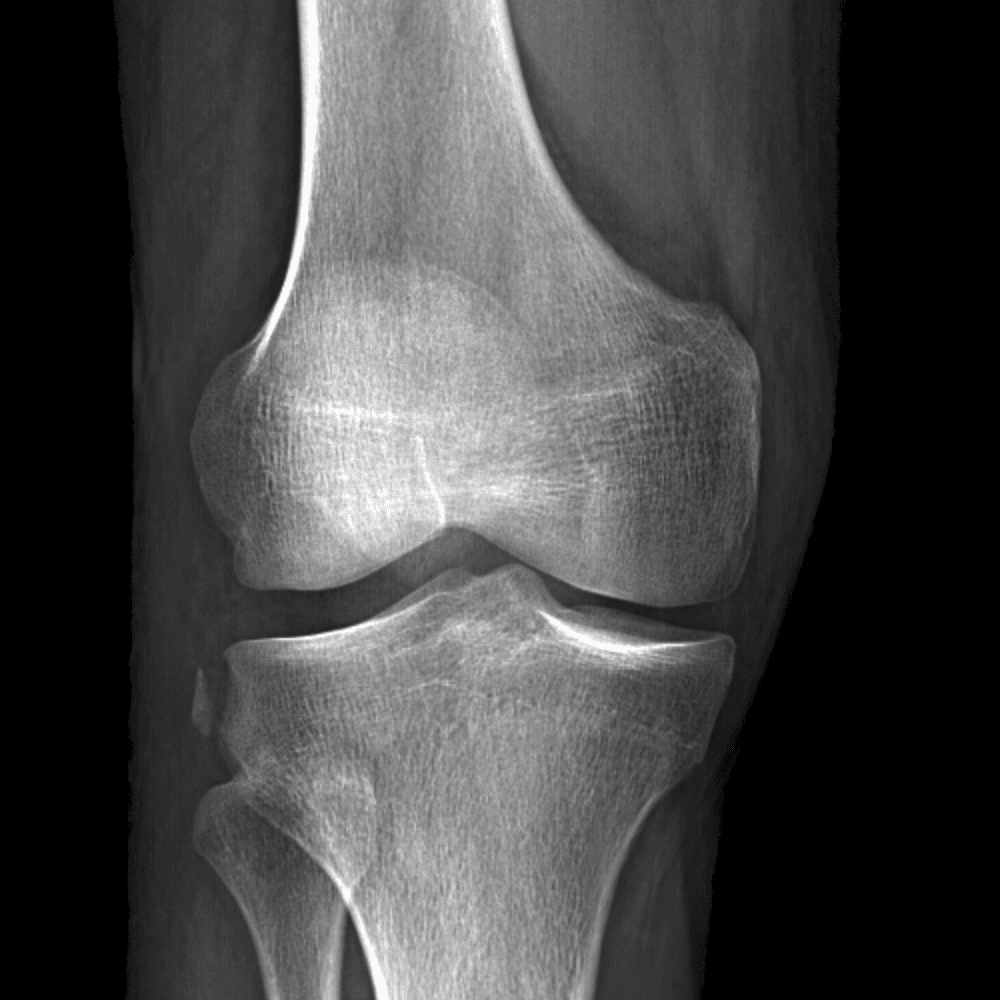

Simula o plantão incluindo casos sutis ou difíceis e alguns normais.